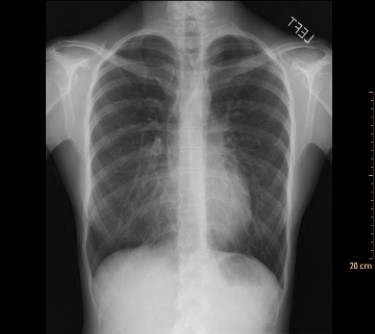

This frontal radiograph suggests an increase in lung density associated with an apparent silhouette sign along the right border of the heart. However, after a lateral view was also examined, the radiologist concluded that the patient's lungs were normal. Why?